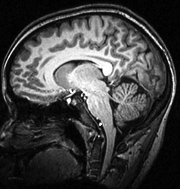

The scanner provides a visual cross-section of the brain in real time, but uses a non-invasive technique that does no harm to living tissue. However, because the MRI generates a magnetic field that is about 60,000 times stronger than the Earth's, not even the smallest piece of iron or steel can be brought safely into the room with it.

MRI scanners in hospitals and other clinical settings often are used to probe the entire body to reveal conditions ranging from blood clots in the kidneys to artery disease in the heart, but Princeton's machine is specially designed to focus exclusively on brain study.